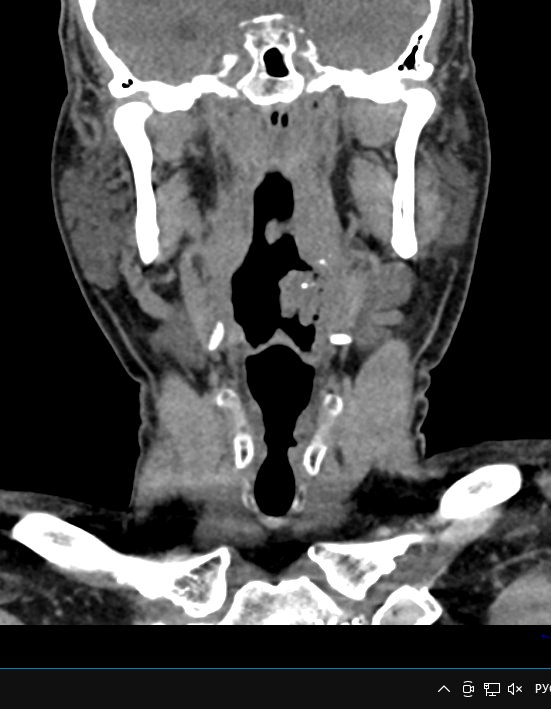

Используемые в нашей клинике томографы, благодаря своему оснащению, позволяют получать снимки высокого качества и детализации за короткий промежуток времени, что минимизирует уровень лучевой нагрузки на организм. Используя полученные данные, аппараты создают трехмерные реконструкции анатомической зоны. Это дает возможность наглядно оценить пространственное соотношение лимфатических узлов и близлежащих органов, выявить прорастание в окружающие ткани, особенно при образовании цепочек, пакетов и конгломератов лимфоузлов.

Для повышения качества визуализации лимфоузлов, особенно при подозрении на онкологических процесс, исследование проводится с внутривенным болюсным контрастированием. Контрастный препарат, содержащий йод, вводится в вену с помощью автоматического шприца. Распространяясь по сосудистой системе, препарат накапливается в патологических очагах, в том числе, в измененных лимфоузлах, и увеличивает их яркость на КТ-изображениях. Методика контрастирования помогает выявлять опухоли минимальных размеров, проводить дифференциальную диагностику между доброкачественными и злокачественными новообразованиями и воспалительными изменениями.

Мультиспиральная КТ позволяет оценить размеры лимфатических узлов, выявить деформацию их контуров, неоднородность структуры, установить точную локализацию, взаимодействие с близлежащими органами и окружающими тканями, обнаружить инфильтрацию прилегающих структур.